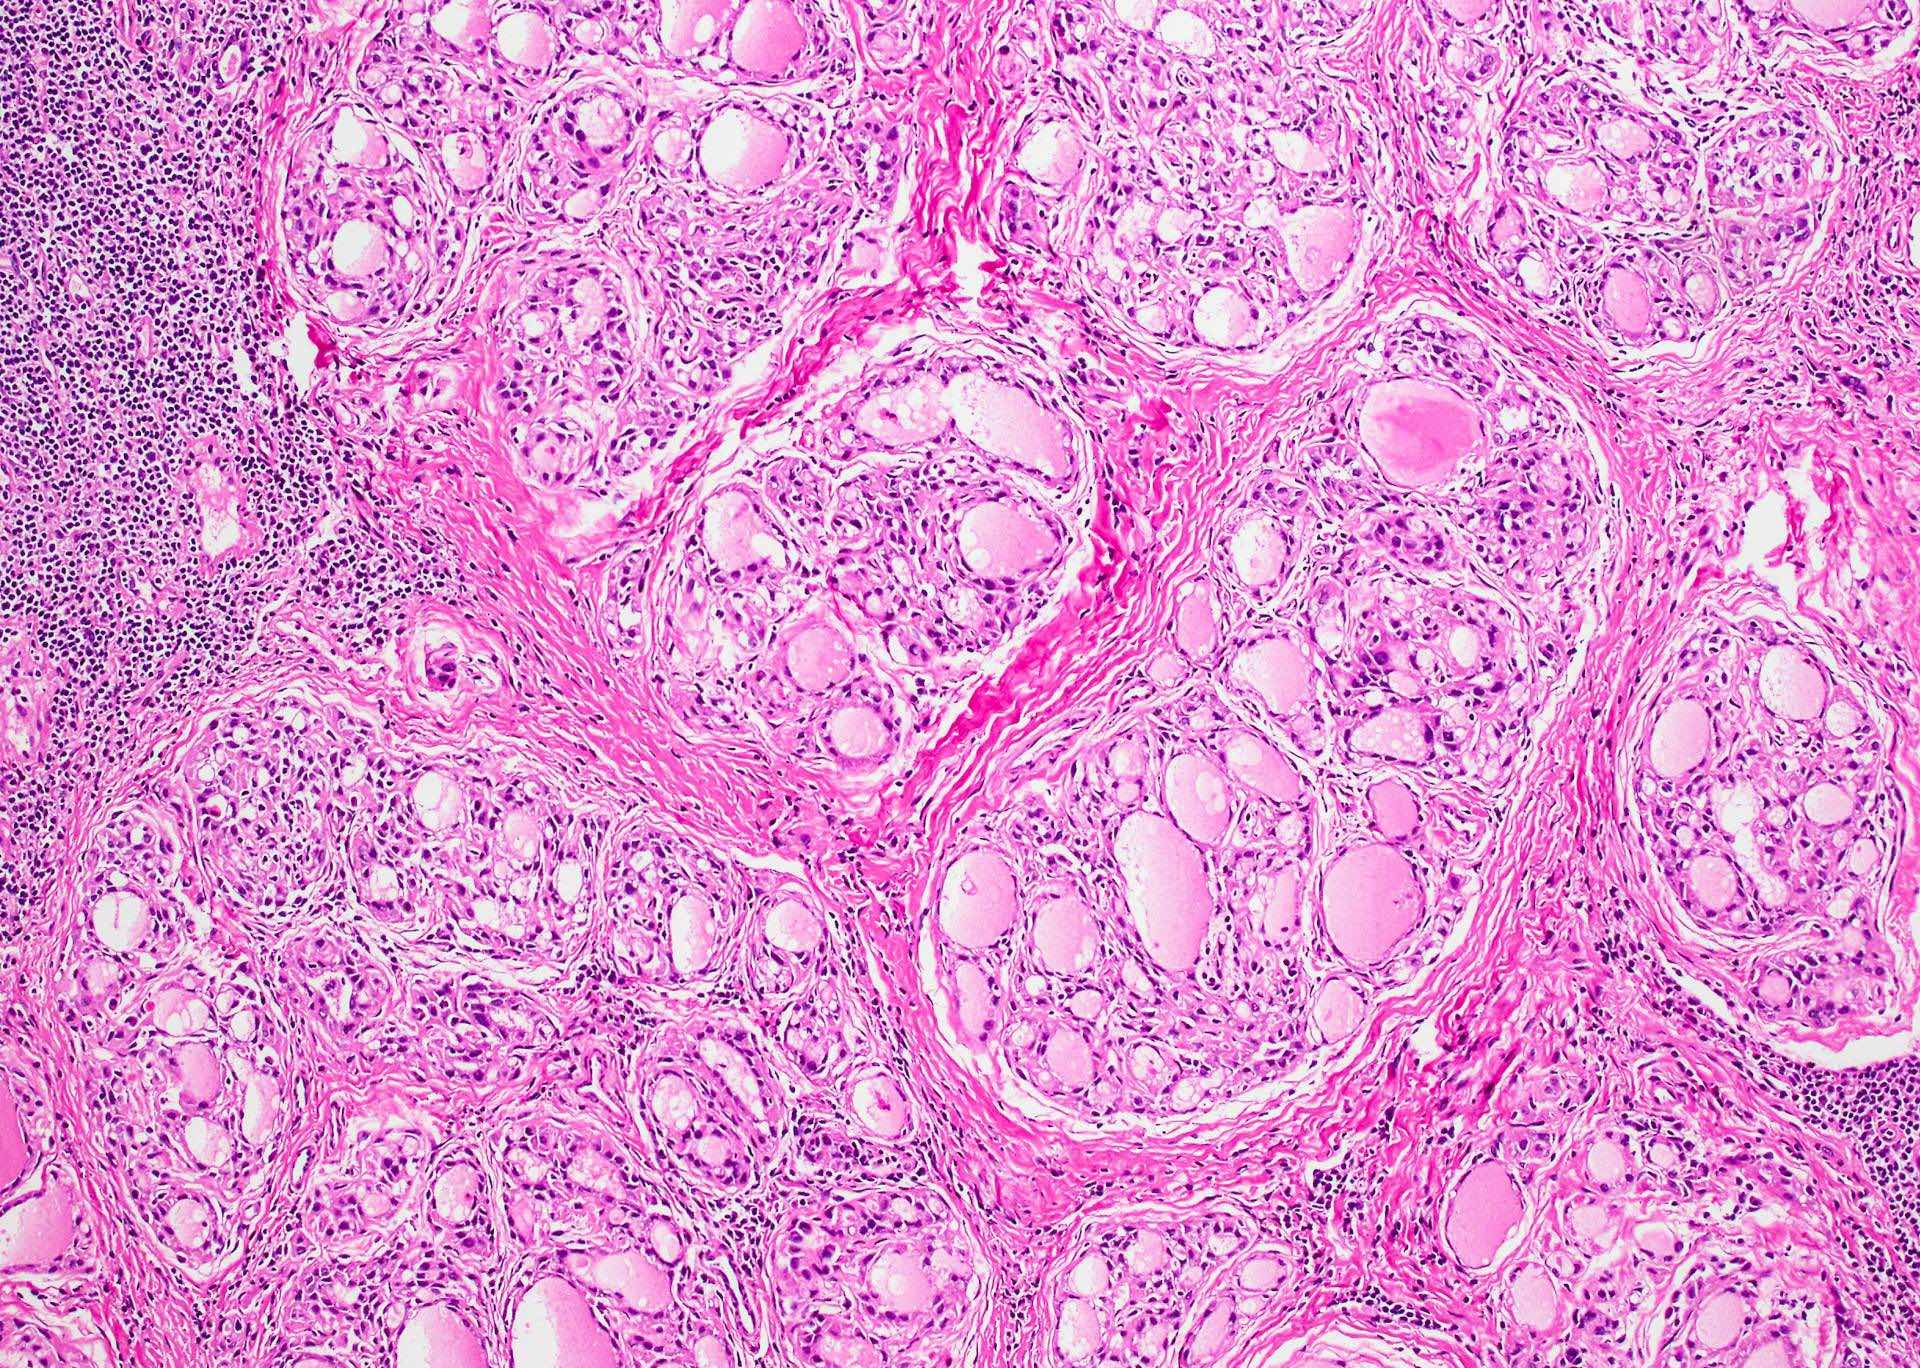

Microscopic (histologic) description

- Classic form: diffuse infiltration of thyroid parenchyma with lymphocytes and plasma cells; lymphoid follicle formation with germinal centers (Best Pract Res Clin Endocrinol Metab 2019;33:101367)

- Later fibrosis and nodularity (Virchows Arch 2013;462:557)

- Fibrous (or fibrosing) variant: extensive keloid-like fibrosis of thyroid parenchyma, fibrous septa divide the parenchyma into lobules, mononuclear cell infiltration, lymphoid follicles, thyroid follicular atrophy, oncocytic cell and squamous metaplasia (Autoimmun Rev 2014;13:391)

Microscopic (histologic) images

Contributed by Andrey Bychkov, M.D., Ph.D. and Shipra Agarwal, M.D.